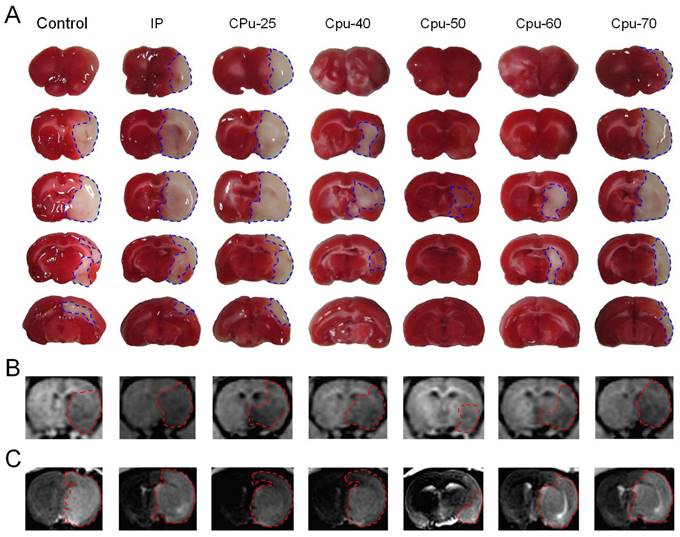

Brain ECS administration of 40-60 mM citicoline significantly reduced brain infarct volume

We found that citicoline administered into rat brain ECS prior to MCA occlusion dramatically reduced the infarct volume compared with that in the control and IP group (Figure 2). We used MRI to define the size of brain infarct lesions and injury severity [4] (Figure 2).

Figure 2

Brain infarct area among different groups. (A) The infarct area of brain slices among different groups. (B-C) MRI images of the brain infarct area among different groups.